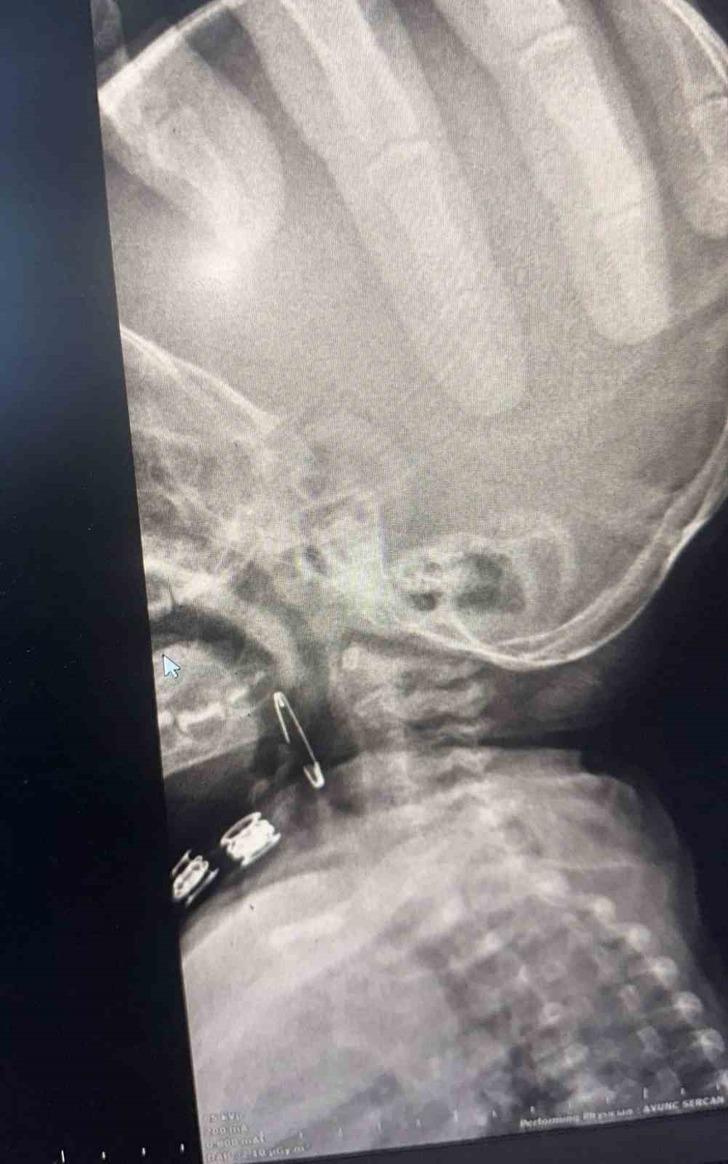

Güroymak ilçesinde 8 aylık bebek, evde bulunan çengelli iğneyle oynarken onu yuttu. Öksürmeye başlayan minik çocuğun, hastanede çekilen röntgen sonucu çengelli iğneyi yuttuğu fark edildi.

Güroymak Devlet Hastanesi’nden Tatvan Devlet Hastanesi’ne ambulansla sevki gerçekleşen minik çocuk, Kulak Burun Boğaz Hastalıkları Uzmanı Operatör Dr. Hakan Tuhan tarafından yapılan başarılı operasyonla sağlığına kavuştu.

Çengelli iğnenin saplı olduğu soluk borusundan çıkarılan bebek, 2 saatlik gözlemin ardından taburcu edildi.

Konuyla ilgili açıklamada bulunan Kulak Burun Boğaz Hastalıkları Uzmanı Operatör Dr. Hakan Tuhan, “8 aylık bir bebek, Bitlis’in Güroymak ilçesinden tarafımıza danışıldı. Güroymak ilçesinde çekilen röntgen sonucunda çengelli iğnenin soluk borusunun girişinde olduğunu teyit ettik. Yapılan müdahaleler sonucunda çengelli iğneyi çıkardık. Çıkardıktan sonra iki saat kadar gözlem altında tuttuk hastamızı. Daha sonrasında herhangi bir komplikasyonla karşılaşmadık ve sorunsuz bir şekilde taburcu ettik” dedi.